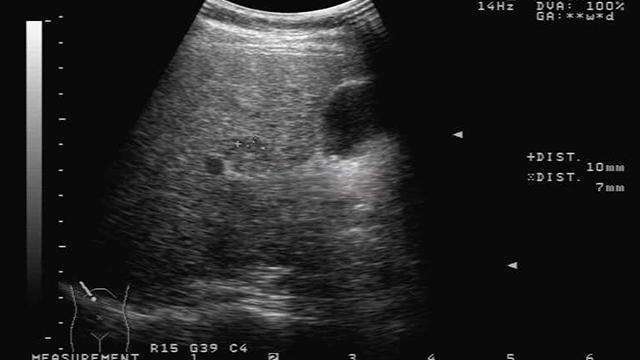

2.肝臟出現結節

在B超檢查中,可以發現肝臟方面有很多的結節,用手去觸碰身體右上腹的皮膚,就感覺到有明顯的包塊,觸感是硬硬的。